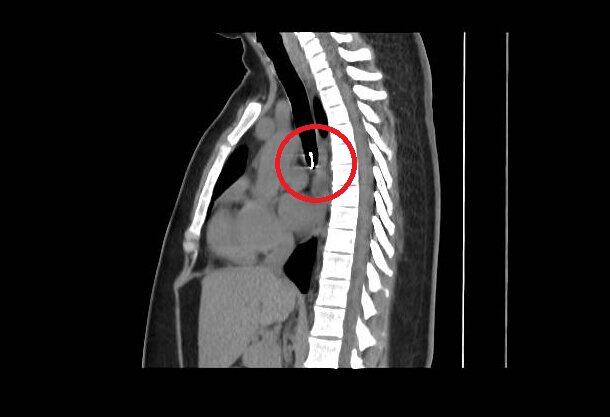

Mesec dana sam uporno kašljala: Lekari nisu mogli da veruju šta su mi pronašli u plućima, 0,5 milimetara od aorte

profimedia-1089210769.jpg

3 / 4

Jam Press / Jam Press / Profimedia